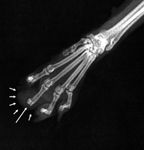

7. A radiograph of the right front foot of the cat in Figure 6 reveals bony destruction involving the third digit (long arrow) and soft tissue swelling (short arrows). (Photograph courtesy of Dr. Laura Garrett.)

The World Health Organization's tumor, node, metastases (TNM) classification scheme for staging tumors has great value when predicting survival time.

8. A lateral thoracic radiograph of the cat in Figure 6 identifies a soft tissue opacity (arrows) involving the left caudal lung lobe. (Photograph courtesy of Dr. Laura Garrett.)